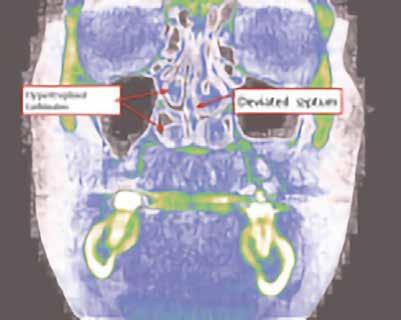

értékelik; azonban ritkán vizsgálják a betegeket az elzáródások eredetére vonatkozóan. Ennek eredményeképpen nagyon gyakran orrelzáródásuk van, és a légutak fizikális vizsgálata vagy képalkotó vizsgálata nélkül kapnak CPAP készüléket, amely a maszk szivárgásával kapcsolatos problémákhoz vezet. Az OSA hatékony kezelési tervének első lépése egy teljes fejre kiterjedő CBCT-vizsgálat elvégzése az elzáródás 4 pontjának meghatározására. (A 4 elzáródási pont (8. ábra) és a CBCT (i-CAT) segítségével történő értékelés részletes magyarázatát lásd az Orthodontic Practice US 2015. márciusi/áprilisi számában [16]). A páciens 4 obstrukciós pontjának – orr-szájpad, orr-garat, velopharynx és oropharynx – vizsgálata kimutatta, hogy a pozíciófüggő apnoe (nyelvalap és velopharynx) mellett orrdugulása is volt (lásd a 9. ábrán látható CBCT-felvételt). Az orrlégúti ellenállás és a BMI a legkorlátozóbb tényezők az OSA-behirdetés

6. ábra: A felvétel a páciens jobb és bal oldali gócszög hipertrófiáját mutatja.

tegek orális készülékterápiával (OAT) történő sikeres kezelésében [17]. Az orrlégúti elzáródás közvetlenül öszszefügg a nappali fáradtsággal [18]. Az i-CAT képalkotó szoftver lehetővé teszi az oropharyngeális légutak volumetrikus értékelését. Ennek a betegnek a kapott adatok alapján súlyosan veszélyeztetett légútja volt, minimum 61,3 mm-rel. A színskála azt mutatja, hogy az értékelés alsó határa 100 mm (9–11. ábra). Kezelési tervünkben OAT (EMA II), fül-orr-gégészeti konzultáció és egy nyomon követő alvásvizsgálat szerepelt. Az FDA által jóváhagyott alvásfogászati készülék 2012. szeptember 5-én került szállításra (12. ábra). A Sibilant Phoneme (Sziszegő fonéma) harapásregisztrációs technikát használtuk a készülék elkészítésének a kiinduló helyzeteként, mivel ez fiziológiai, nem pedig konstrukciós technika. Ez az egyetlen olyan harapásregisztrációs technika, amely bizonyítottan és szakmailag lektorált folyóiratban publikálva jelent meg. Ennek a harapásregisztrációs technikának lényege, hogy megnyitja a légutakat, de amely a legfontosabb, csökkenti azok összeesését [19]. Az OSA-ban szenvedő betegeknél a légzés kizárólag csak alvás közben áll le, ezzel szemben ébrenlét közben soha nem áll le. Így az oropharyngealis légutak térfogata kevésbé fontos, mint azok összeesése. Ez azt jelenti, hogy ritkán van szükség titrálásra, ha a fonetikus harapásregisztrációt kiindulási pontként használjuk. Ez a páciens tökéletes példa erre, mivel az ő készülékét soha nem kellett titrálni. Az orofaringeális térfogatok (13. ábra) az ébrenléti kiindulási állapotban és a harapásregisztrációval csak kis különbséget mutatnak, azonban az

9. ábra: A 3D-s vizsgálat orrkagyló- és orrsövényproblémákat mutat.

10–11. ábra: Légutak számításai különböző nézetekben.